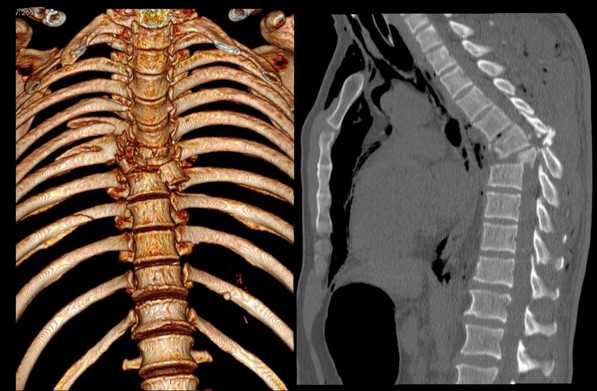

Перелом грудного отдела (трехмерная и сагиттальная проекции)

В результате компьютерной томографии получают серию послойных изображений рассматриваемой зоны. Монохромные фотографии обладают высоким разрешением. В отличие от рентгенографии на снимках отсутствуют дефекты и тени от расположенных рядом структур. Изменение плоскости при реконструкции изображений позволяет тщательно изучить анатомические образования. Преимуществом КТ является возможность создания 3D-модели позвоночника.

Для усиления информативности сканирования используют контрастирование. В качестве “окрашивающего” вещества применяют раствор йода, обладающего высокой поглощающей способностью в отношении рентгена.